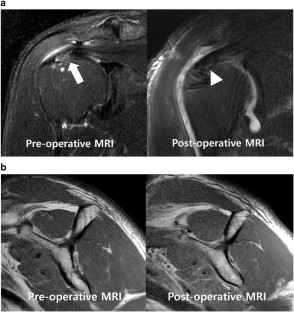

Fig. 4